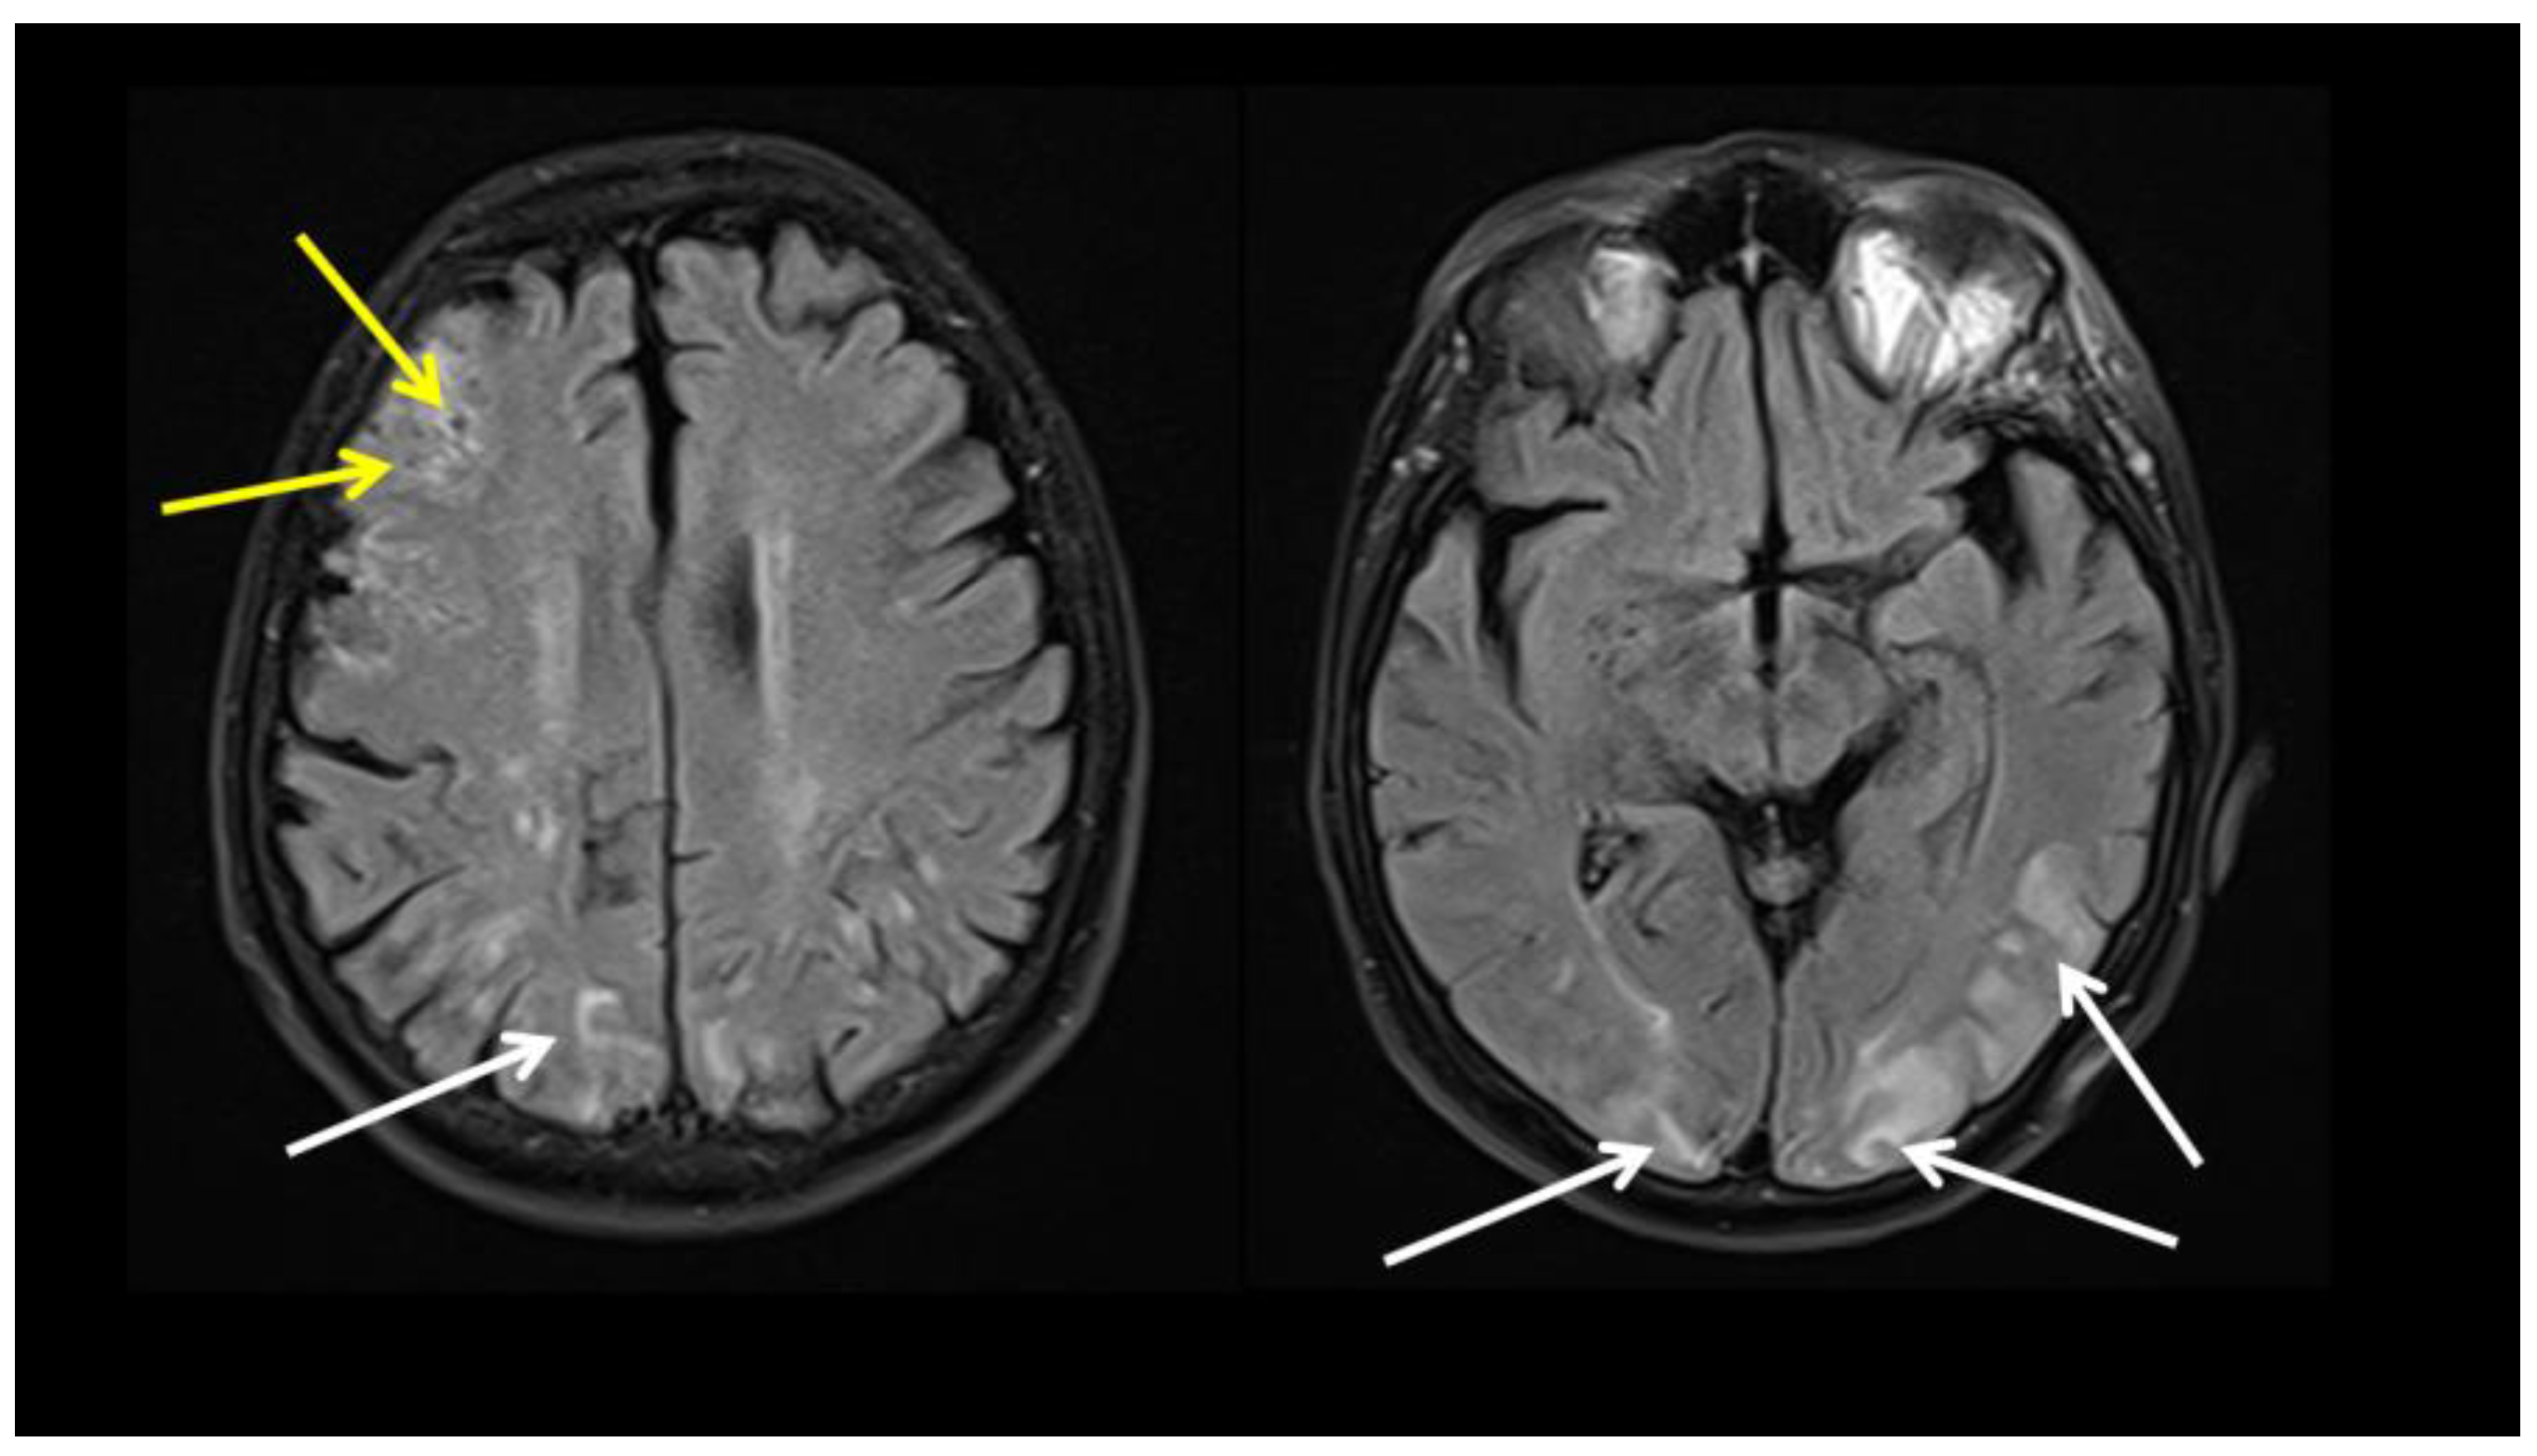

| Author | Age/Sex | Clinical Presentation, Laboratory Findings | Timing of Symptoms after COVID-19 | Diagnosis | Treatment | Testing | Outcome |

|---|---|---|---|---|---|---|---|

| Oda R, et al., 2020 [5] | 73 years, male | Persistent spiking fever, elevated ESR and CRP | concomitantly | LV-GCA | NSAID | CTA, FDG PET-CT | Recovered without treatment |

| Riera-Marti N, et al., 2021 [22] | 50 years, male | High fever, headache, temporal artery thickening, TM joint pain | concomitantly | c/LV-GCA | No treatment | Doppler US FDG PET-CT | Recovered without treatment |

| Jonathan G, et al., 2021 [7] | 47 years, male | PAAM, headache, jaw claudication | 8 weeks | PAMM TAB–negative GCA | High dose CS Tocilizumab | Ophthalmic diagnostic tests, TAB | Improvement on treatment |

| Ivanovic J, et al., 2022 * [8] | 69 years, male | Headache, fever, elevated ESR, CRP, Fib, IL-6 | 6 weeks | LV-GCA Cerebral vasculitis | High dose CS, TPE Tocilizumab, IVIG, AZA | FDG PET CT Brain MRI | Improvement on treatment |

| Aryal B, et al., 2022 [20] | 72 years, female | Headache, blurred vision, transient vision loss, abdominal pain | 8 weeks | TAB-negative GCA | High dose CS, AZA, MTX | Clinical presentation Laboratory tests | Improvement on treatment |

| Szydełko-Paśko U, et al., 2022 [6] | 69 years, female | Vision loss [left eye] Headache | 2.5 weeks | AAION c-GCA | High dose CS, MTX | Ophthalmic diagnostic tests | Improvement In treatment |